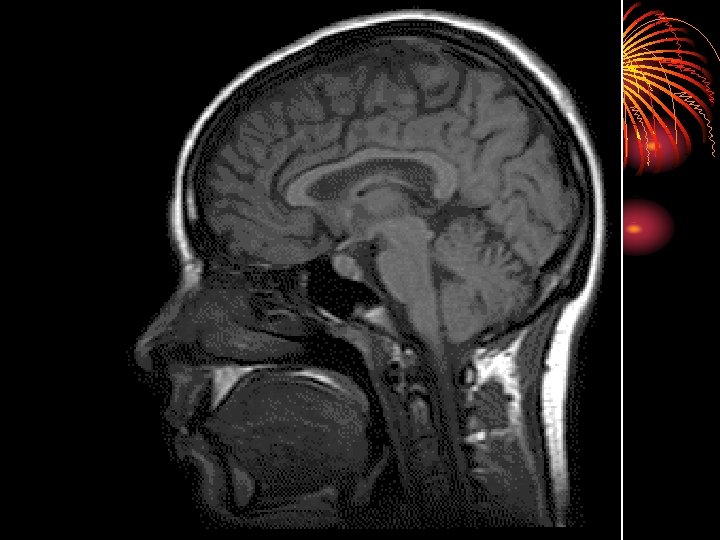

• Magnetic Resonance Imaging (MRI) • A technique that uses magnetic fields and radio waves to produce computergenerated images that allow us to see structures within the

I. The Hindbrain

• The hindbrain is the oldest and innermost region of the brain

II. The Midbrain • The Midbrain is located between the hindbrain and the forebrain • This area is responsible for coordinating simple muscle movements with changes in sensory information

III. The Forebrain • Areas of the forebrain control thought and reason. • There are five main regions of the forebrain to study: • Thalamus • Hypothalamus • Amygdala • Hippocampus • The Cerebral Cortex

• The CEREBRAL CORTEX is the intricate, wrinkled covering of the brain (FISSURES) (actually a bump is a gyrus and a groove is a sulcus – but that’s a bit too much info…) • In addition to interneurons, it contains GLIAL CELLS, which guide neural connections, provide nutrients to myelin, and mop up neurotransmitters

• The two hemispheres of the brain are connected by the CORPUS CALLOSUM